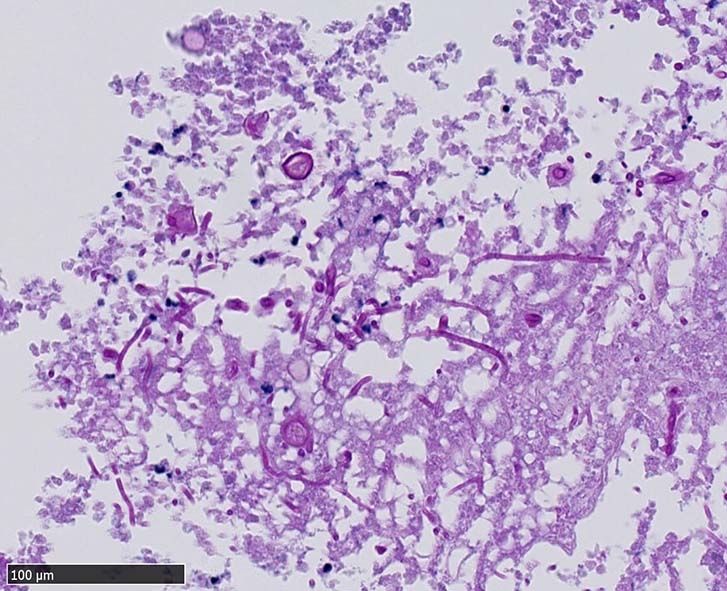

空洞辺縁には5~50μm径ほどの球状体(spherule)が形成され, 大型の球状体の一部は内部に2~10μm径ほどの内生胞子(endospore)を容れている. 内生胞子はPAS, Grocottで染色される.

本症例では空洞壁部分に球状体のほか多数の菌糸発育が観察された.

栄養型(菌糸および分節型分生子)と寄生型(内生胞子を多数容れた球状体)*1